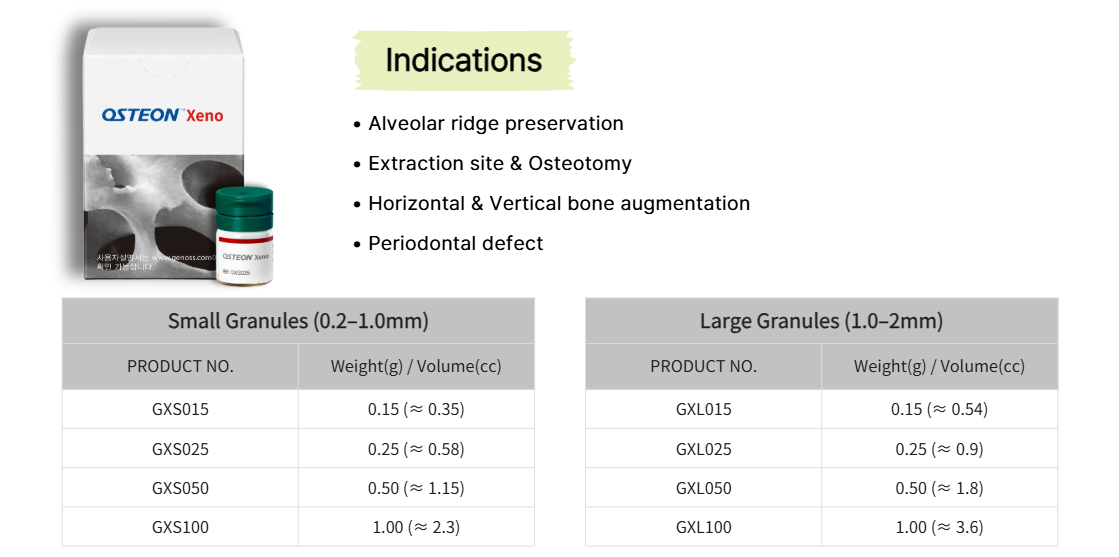

Wide Range of Options

OSTEON™ Xeno is designed to accommodate a wide range of surgical conditions, allowing clinicians to select and apply it flexibly according to clinical requirements.